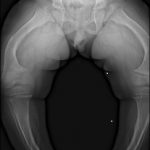

TRANSIENT OSTEOPOROSIS OF THE HIP

This is a curious condition without obvious etiology. It is characterized by loss of bone density in one of the hips of the affected person. It is usually found in middle aged men and sometimes in pregnant women. The condition usually clears up within a few months. It can be painful if the bone is under strain therefor, treatment consists of partial weight bearing to alleviate pain.